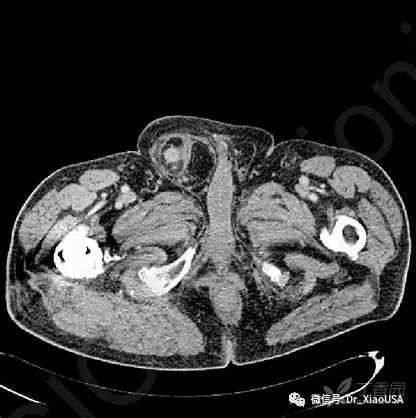

20.结肠梗阻的典型CT表现有哪些?

a) 结肠扩张

b) X交叉征(X-marks-the-spot):提示结肠扭转

i. 一个部位出现2个扭转点(近端- B和远端- C),每个扭转点轴心线相互垂直(X征,黄色长箭头标志)

c) 结肠壁分裂(split the wall):提示不完全结肠扭转

i. 两段扭转的结肠(短黄箭头)由肠系膜(长黄箭头)分开

d) 盲肠吊桥征(cecal bascule):提示盲肠扭转

i. 盲肠向前上翻转形成一个折叠带(白色短箭头)